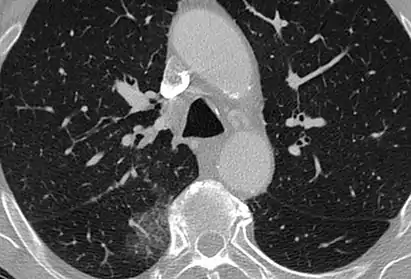

Ground-glass opacity is among the most common imaging findings in patients with confirmed COVID-19.[16][17] One systematic review found that among patients with COVID-19 and abnormal lung findings on CT, greater than 80% had GGOs, with greater than 50% having mixed GGOs and consolidation.[16] GGOs with mixed consolidation has most often been found in elderly populations.[18] Several studies have described a pattern among initial, intermediate, and hospital discharge imaging findings in the disease course of COVID-19. Most commonly, initial CT imaging reveals bilateral GGOs at the periphery of the lungs. During initial stages, this is most often found in the lower lobes, although involvement of the upper lobes and right middle lobe has also been reported early in the disease course.[16][18] This is in contrast to the two similar coronaviruses, SARS and MERS, which more commonly involve only one lung on initial imaging.[19][20] As the COVID-19 infection progresses, GGOs typically become more diffuse and often progress to consolidation.[11][18] This is sometimes accompanied by the development of a crazy paving pattern and interlobular septal thickening.[18] In many cases the most severe pulmonary CT abnormalities occurred within 2 weeks after symptoms began.[17] At this point, many individuals begin showing resolution of consolidation and GGOs as symptoms improve. However, some patients have worsening symptoms and imaging findings, with further increase in septal thickening, GGOs, and consolidation. These patients may develop lung "white-out" with progression to acute respiratory distress syndrome (ARDS) requiring treatment escalation.[17][21]

Preliminary reports have shown many patients have residual GGOs at time of discharge from the hospital. Due to the novelty of COVID-19, large studies investigating the long-term pulmonary CT changes have yet to be completed. However, long-term pulmonary changes have been seen in patients after recovery from SARS and MERS, suggesting the possibility of similar long-term complications in patients who have recovered from acute COVID-19 infection.[22]